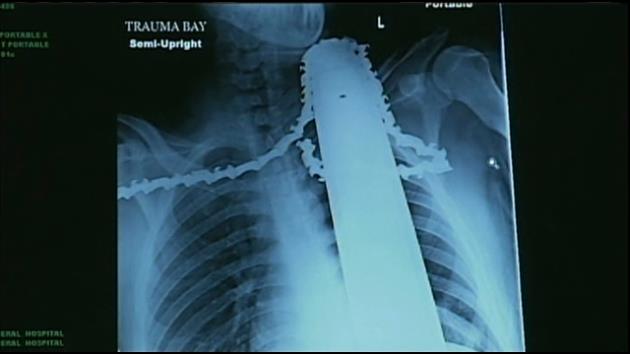

Valentine had emergency surgery at Allegheny General Hospital. Doctors say the saw missed major arteries and instead cut into muscle. The hospital Tuesday released an X-ray showing the saw still in the 21-year-old’s neck.